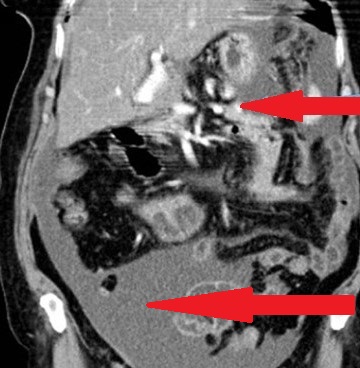

Red arrows — transition point. Multiple air-fluid levels (Courtesy Dr. V. Penopoulos)

The two metastatic foci causing stenosis and bowel obstruction are clearly visible (Courtesy Dr. V. Penopoulos)